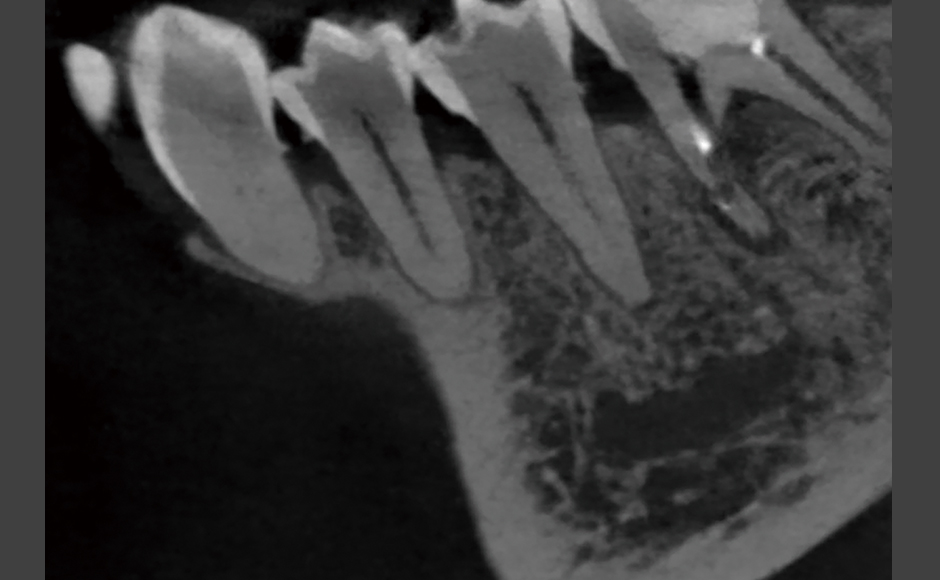

症例.1:穿孔を伴う根尖性歯周炎に対して非外科的歯内療法を行った症例

症例.2:外科的歯内療法を併用して根尖性歯周炎の治療を行った症例